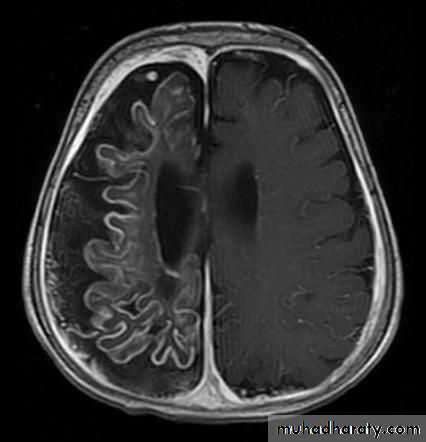

• This syndrome is a sporadic disorder and consists of a constellation of symptoms and signs including a facial nevus (port-wine stain), seizures, hemiparesis, stroke like episodes, intracranial calcifications, and, in many cases, mental retardation.• Clinical manifestations

• 2- Brain CT scan: to detect the extent of the calcification that is usually associated with unilateral cortical atrophy and ipsilateral dilatation of the lateral ventricle.

• 3- MRI is a useful to detect the location of the vascular malformation and the presence of white matter lesions.